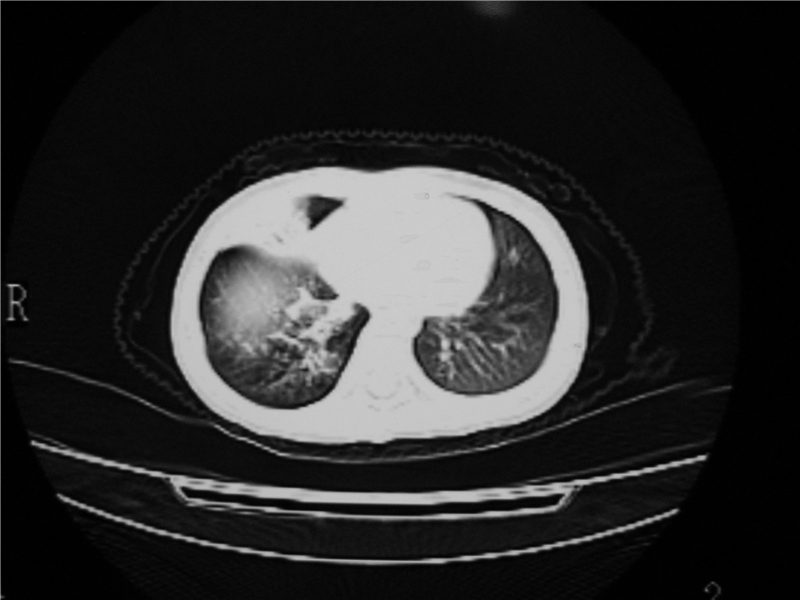

右肺中叶及下叶内段大片实变密度增高影,可见支气管气象,肺炎.

摄吸气及呼气相对比片,本例为有肺中叶阻塞性炎症、不张,右肺下叶阻塞性炎症。

1)右肺炎症并右肺中叶肺不张,右肺上叶充气不良。2)右侧支气管异物不排除。